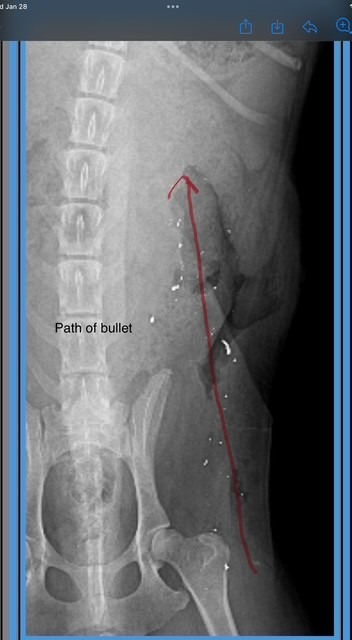

Further examination revealed shrapnel embedded in his wound. X-rays confirmed that Marty had been shot. The bullet entered through his rear and exited through his back, leaving behind a large, infected hole. Marty has been hospitalized for about a week now and continues to receive daily, intensive treatment. He is still very sick and extremely fragile.